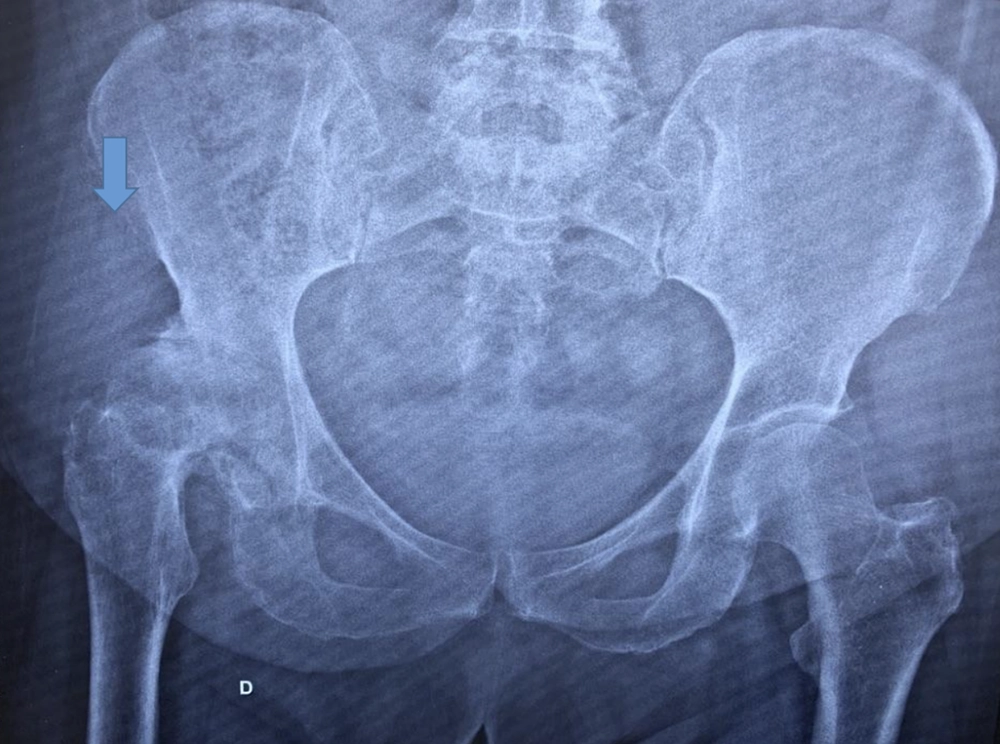

Seguem abaixo, alguns exemplos:

Artrose severa quadril direito – seta.